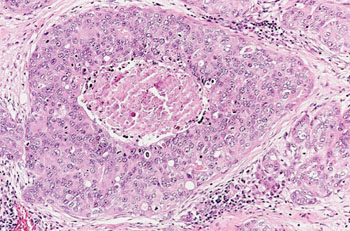

图片:乳腺组织的组织病理图像显示重度乳腺癌(图片蒙约翰霍普金斯医学院惠赐)。

可按照风险和频率把乳腺癌易感基因或基因座分为三类,但现在日益增多的风险基因名单上又多了四种基因。